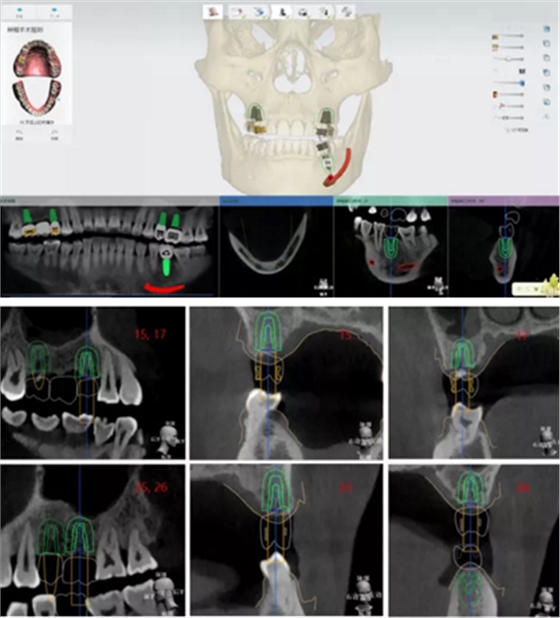

植體植入設(shè)計

設(shè)計植入5顆種植體

查看種植體螺絲通道穿出虛擬修復(fù)體的位置。

查看種植體在牙槽嵴頂穿出位置。

規(guī)劃種植導(dǎo)板